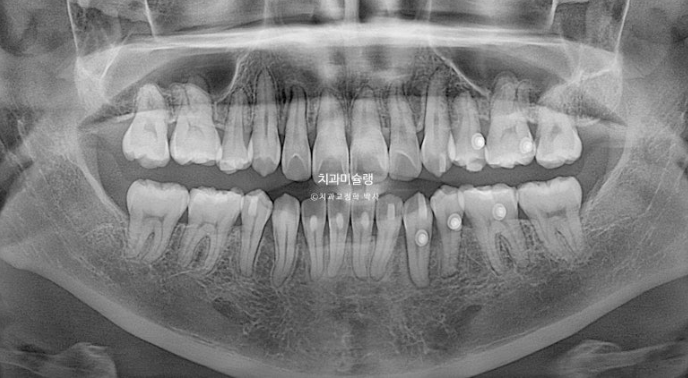

23.10

23년 10월 교정치료를 이해 온 30대 환자분입니다.

약 2mm 정도의 중심선 불일치 그리고 덧니가 보입니다.

개방교합도 있고

30년간 공간이 없어서 미처 내려오지 못한 작은어금니도 있습니다.

덧니가 워낙 심해 작은어금니 4개 발치가 불가피한 상황입니다.

2년 3개월의 치료기간동안 치근흡수는 없고 치근평행도는 양호합니다.